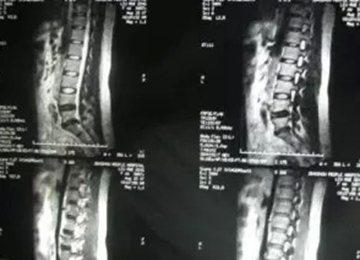

案例二

核磁矢状位

核磁轴位

2011年,小张(20岁),L4-5椎间盘脱出,高密人民医院、青岛山大医院要求手术。右腿外侧疼痛,迈不开步子,直腿抬高不过20°。